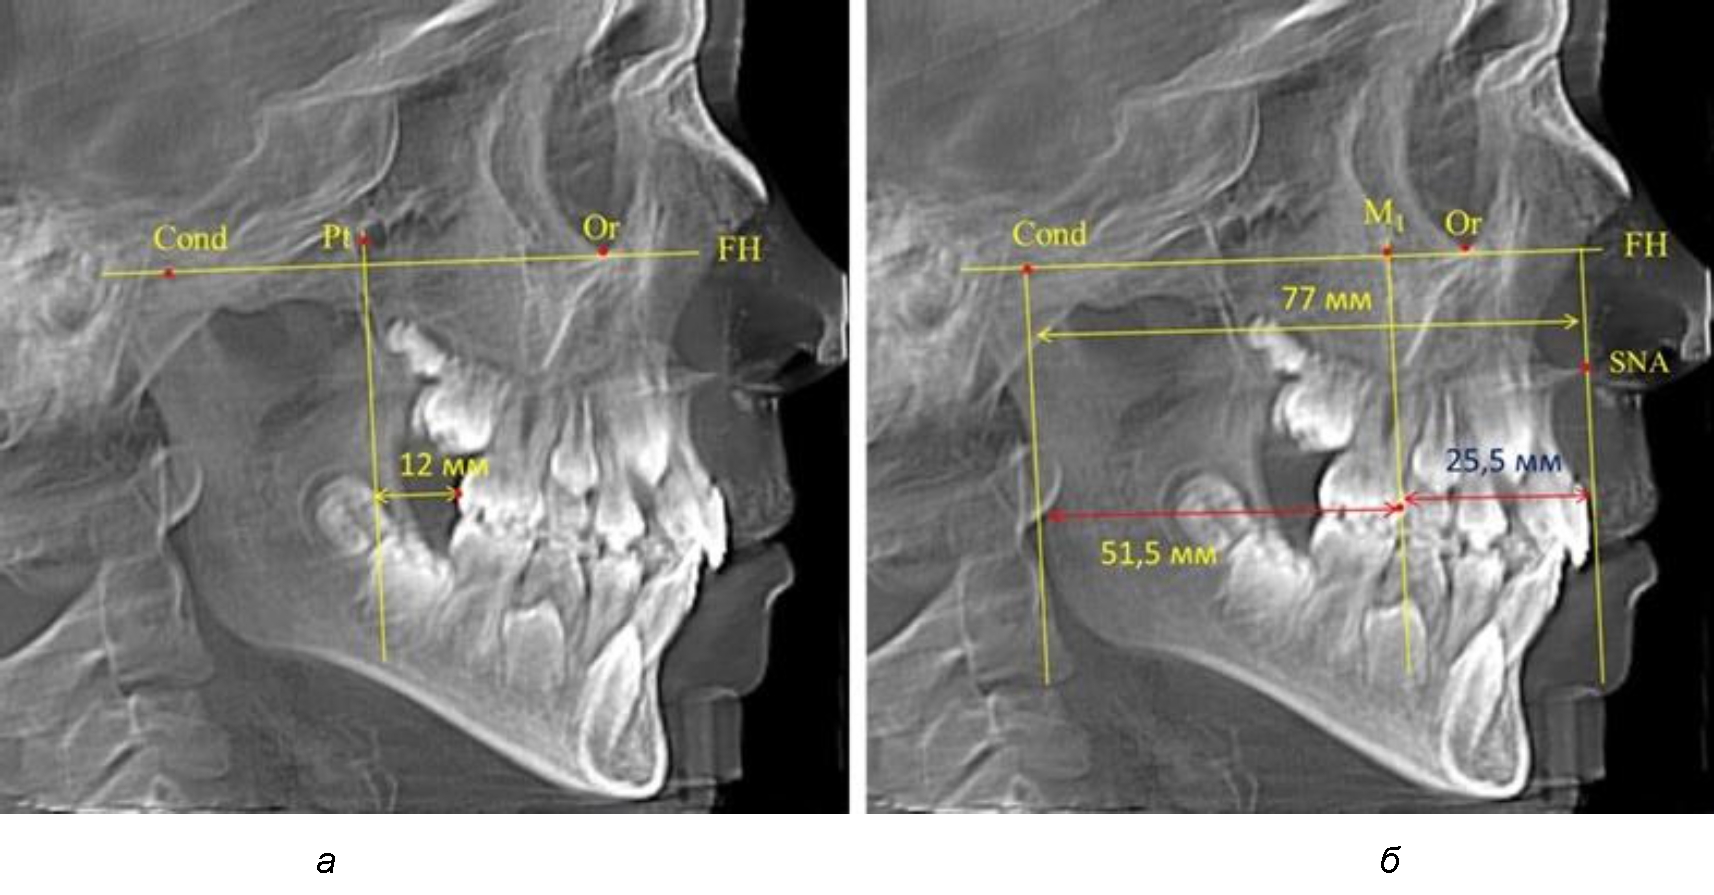

Рис. 3. Особенности положения первых моляров по R. E. McDonald (а) и по предложенному методу (б) при увеличенном молярно-крыловидном расстоянии

В то же время при увеличенном расстоянии от крыловидной вертикальной плоскости PTV до дистальной поверхности верхнего первого постоянного моляра, равное 23 мм, сагиттальный размер гнатического отдела составил 92 мм. При этом отношение кондилярно-спинального расстояния к кондилярно-молярному размеру (30,5), так же, как и при малых размерах, было близким к коэффициенту 1,5, что представлено на рис. 3.

Таким образом, наблюдалась эффективность использования относительных показателей при определении положения первых постоянных моляров. При этом наиболее целесообразно и с методологической точки зрения верным, было использование медиальной поверхности первого постоянного моляра. Построенная таким образом молярная линия отграничивала отдел зубной дуги с замещающими зубами от дистального отдела с добавочными зубами постоянного прикуса, в частности, постоянных моляров.

Среднее расстояние между суставной (кондилярной) и спинальной вертикалями в анализируемой группе составило (89,12 ± 2,8) мм. При этом сагиттальный размер в среднем составлял (58,74 ± 1,57) мм, а передний размер был (30,41 ± 1,02) мм. Несмотря на вариабельность размеров и большую ошибку репрезентативности, относительно стабильным показателем было отношение сагиттального размера гнатического комплекса к заднему отделу, которое составляло в среднем 1,5 ± 0,06.